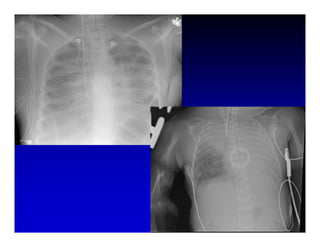

1. High frequency ventilation (HFV) uses small tidal volumes and high respiratory rates to ventilate patients with acute lung injury (ALI) or acute respiratory distress syndrome (ARDS). HFV aims to recruit and protect the injured lung better than conventional mechanical ventilation (CMV). 2. Two main types of HFV are high frequency oscillatory ventilation (HFOV) and high frequency jet ventilation (HFJV). HFOV uses a piston to displace gas at 180-900 breaths per minute, while HFJV uses gas jets at 240-480 bpm. 3. Early intervention with HFV may improve outcomes compared to using it as a rescue therapy after prolonged CMV fails. Matching the